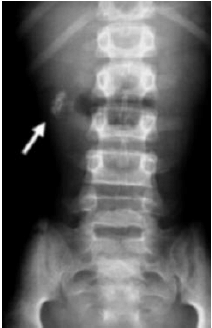

Observe a radiografia abaixo e indique a principal hipótese diagnóstica: